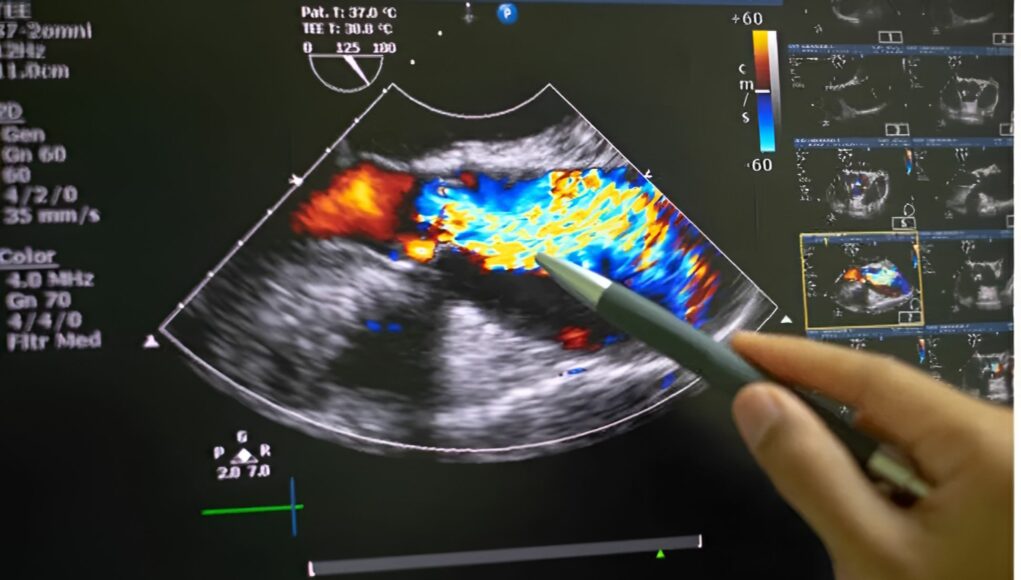

L’ecografia addominale è un esame diagnostico, altamente informativo, non invasivo, indolore basato sugli ultrasuoni. Il principio è lo stesso che usano i pipistrelli per orientarsi, vengono emessi dei suoni che rimbalzando sugli ostacoli che trovano nella loro strada, il muro di una caverna per un pipistrello, o i nostri organi nel caso di un ecografia. Una volta ritornati alla sonda, che scivola dolcemente sulla pelle dopo l’applicazione di un gel, gli ultrasuoni producono un’immagine che permette di vedere perfettamente all’interno del nostro corpo. L’esame si svolge in circa 15-30 minuti, data la quantità di informazioni che raccoglie è un tempo veramente esiguo, richiede però una leggera preparazione come altri esami, ad esempio potrebbe essere richiesto di presentarsi all’esame a digiuno, di assumere carbone vegetale al fine di ridurre i gas intestinali, o di recarsi all’esame con la vescica piena permettendo di visualizzare meglio la vescica. é un esame tenuto sempre in considerazione data la sua velocità, versatilità e ripetibilità senza rischi.

Essendo l’addome una zona del corpo dove si concentrano molti organi, una sola ecografia è in grado di fornire una panoramica approfondita e individuare svariate patologie definendosi come un esame utile e importante per la diagnostica e la prevenzione.

Gli organi riguardo i quali è possibile rinvenire informazioni tramite ecografia addominali sono il fegato, la cistifellea, il pancreas, i reni, la milza, la vescica, la prostata, l’utero, l’aorta addominale, e parte dell’intestino.